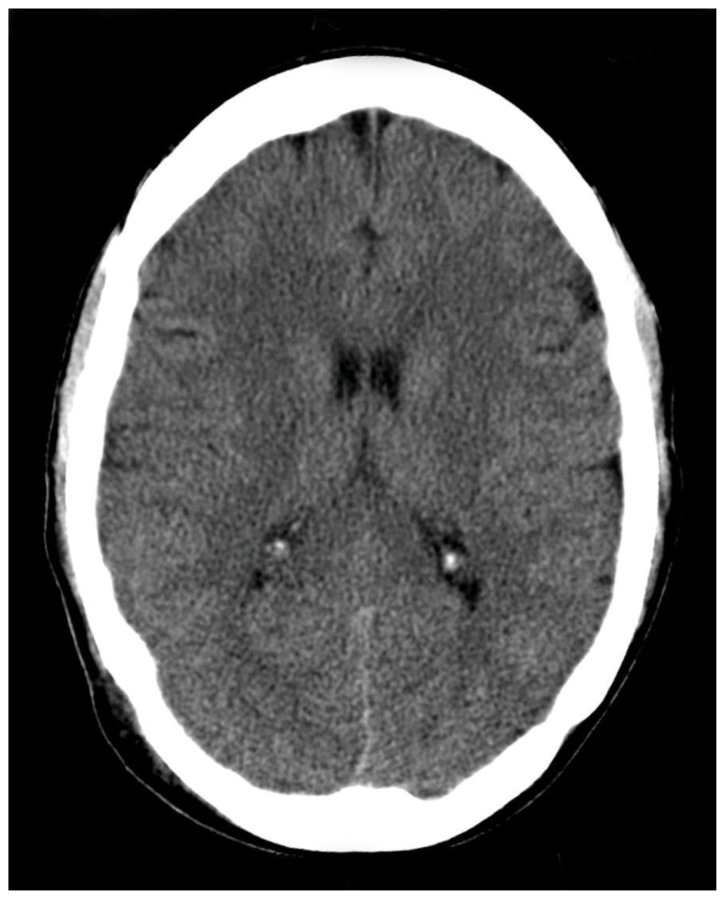

| #7 | Head-CT |

- List appropriate laboratory and imaging studies to include complete blood count (CBC), complete metabolic panel (CMP), magnesium level, and computed tomography (CT) scan of the brain.